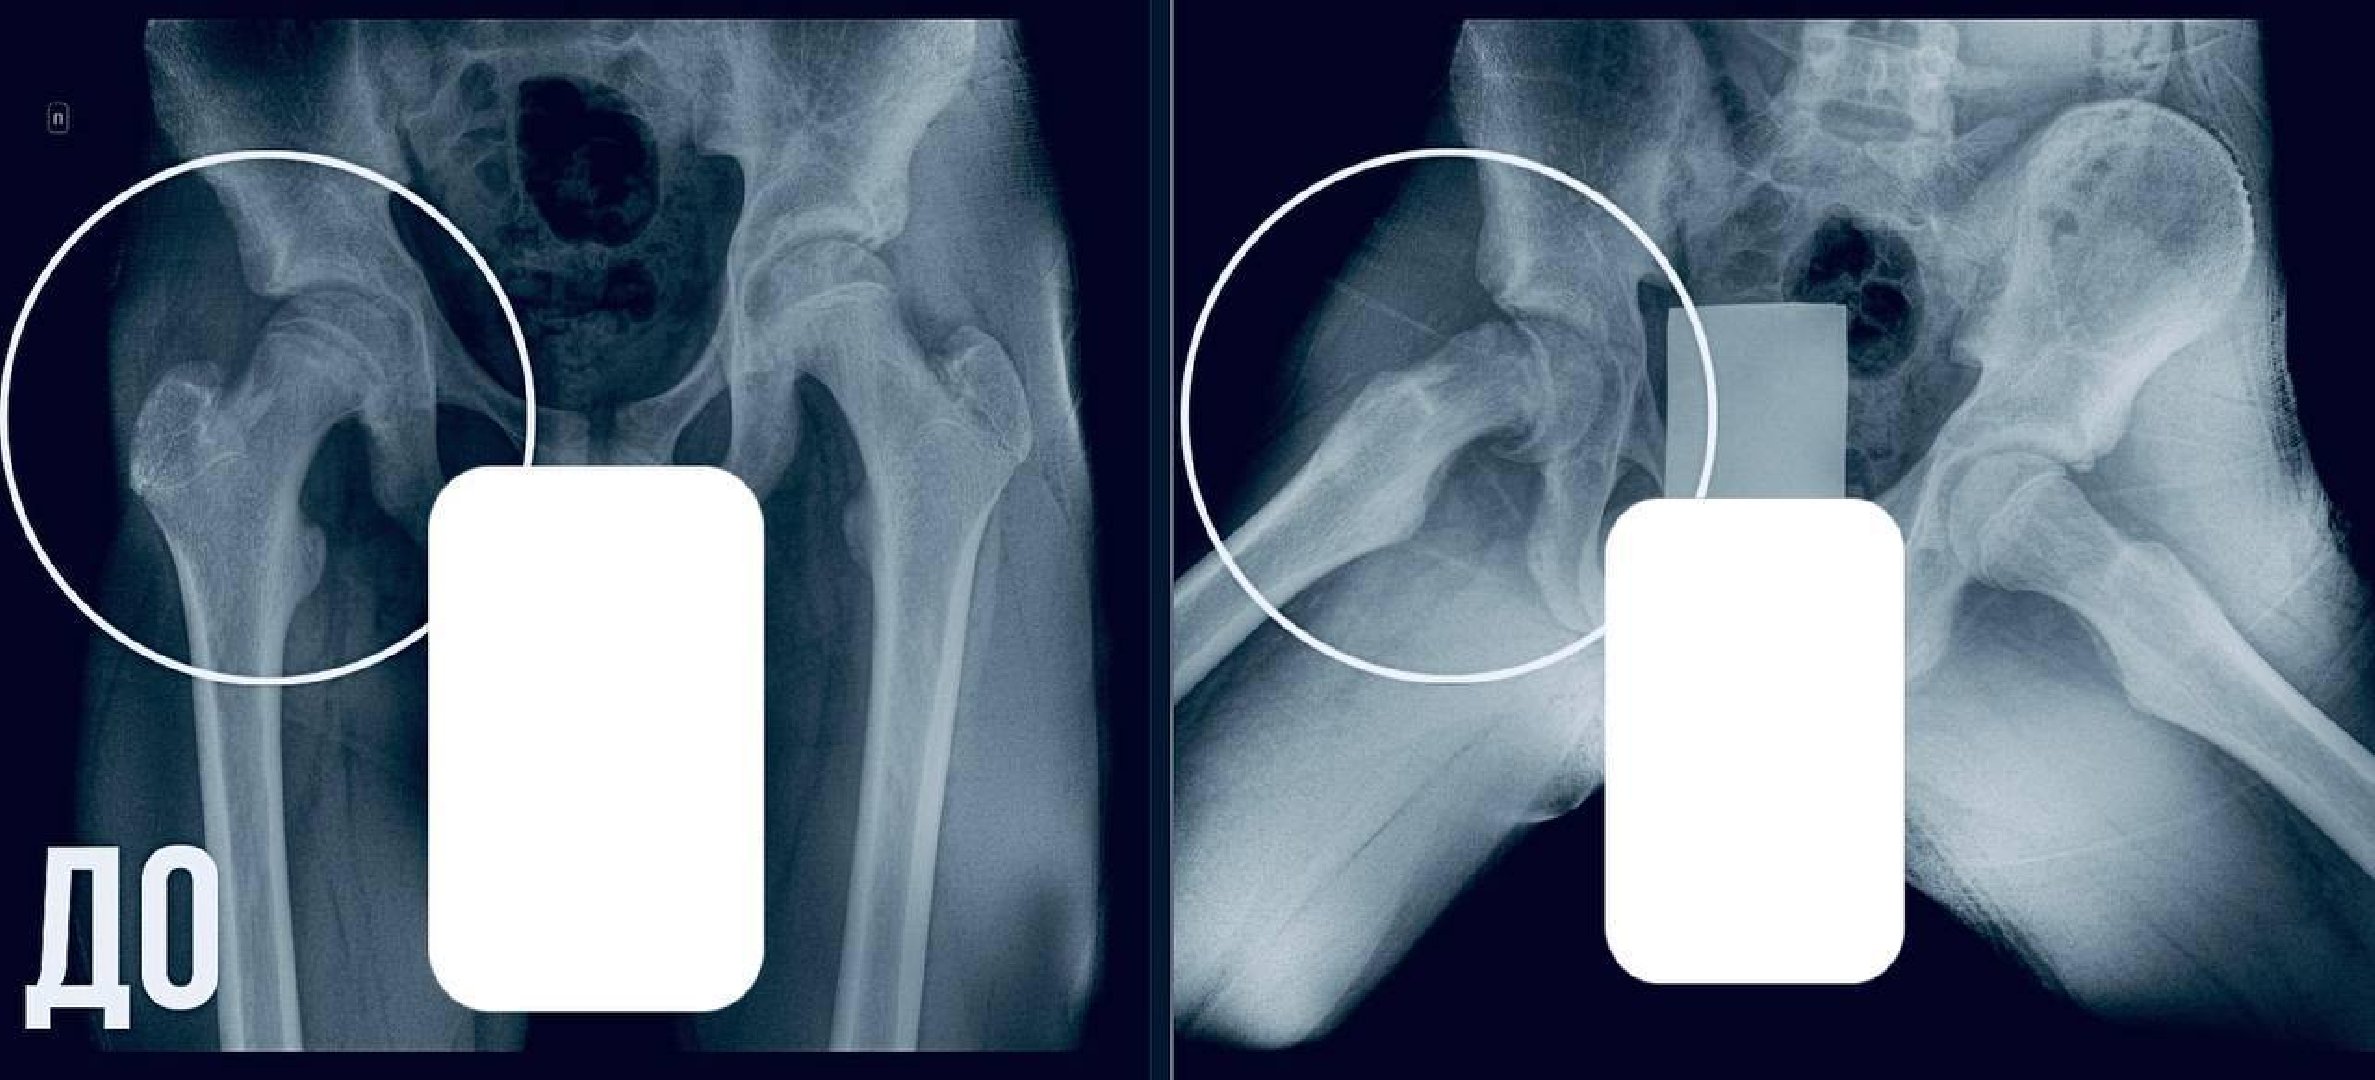

Родители обратились в Московскую областную детскую клиническую травматолого-ортопедическую больницу, где на обследовании выявили юношеский эпифизеолиз — смещение головки бедренной кости, характерное для периода активного роста.

«Пациенту требовалась срочная операция. Мы выполнили фиксацию сустава, чтобы остановить смещение и дать ему возможность правильно развиваться. Это убережет юношу от раннего артроза и ограничений подвижности в будущем», — отметил главный врач МОДКТОБ Александр Григорьев.Сейчас подросток идет на поправку. В ближайшее время его выпишут домой, после чего он начнет курс реабилитации. Врачи советуют родителям не откладывать визит к врачу, если ребенок хромает, у него боли в бедре или неустойчивая походка. Своевременное обращение поможет избежать серьезных осложнений.